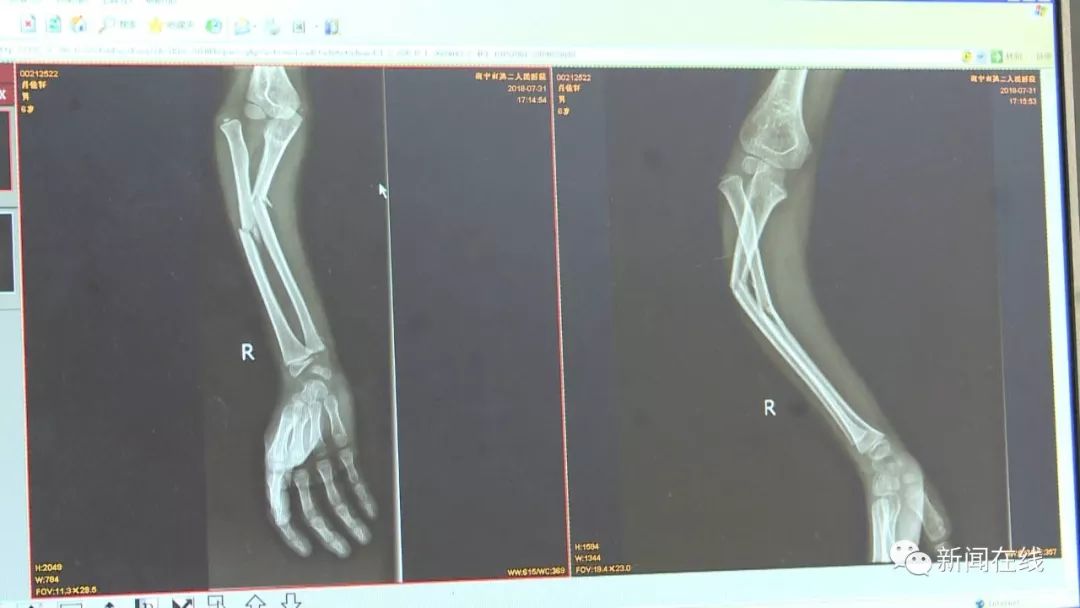

六岁男孩万达玩蹦蹦床,手臂被踩骨折脱臼别让

在万达茂玩蹦蹦床,六岁男孩右手臂被踩骨折脱